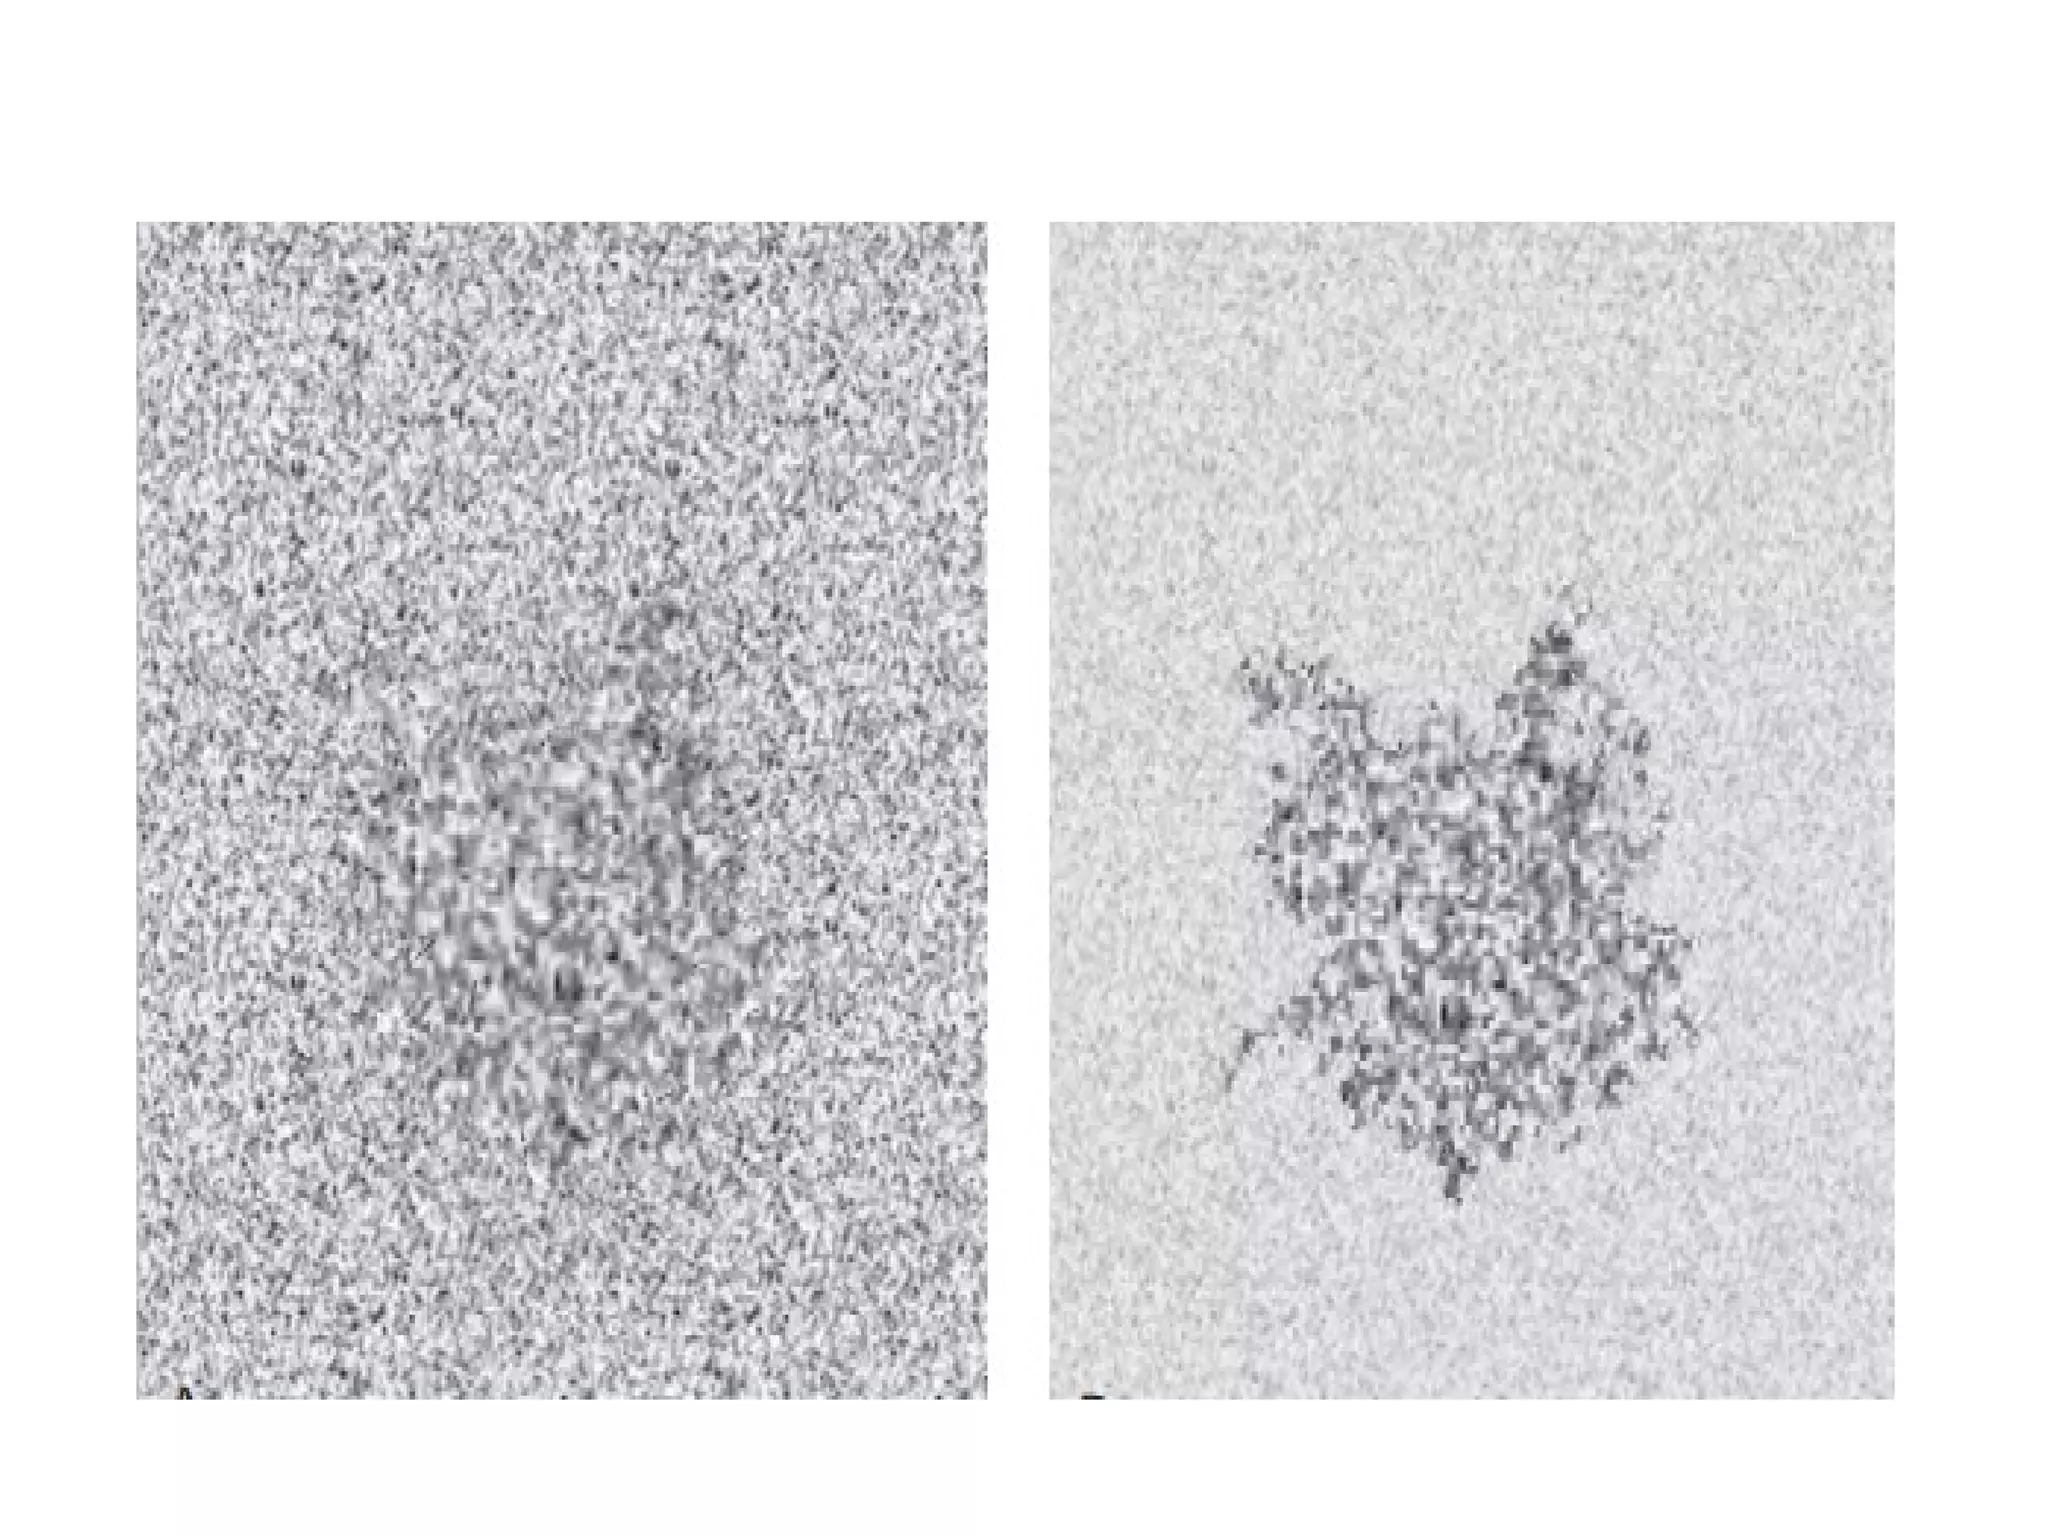

Power Doppler :

• Power Doppler displays the power (or intensity)

of the Doppler signal, as it changes with time in

every region within the chosen area.

• However, there is no information available

regarding the velocity.

• The power Doppler has superior flow sensitivity

as compared to conventional color Doppler.

• So it is used to evaluate the presence and

characteristics of the flow in blood vessels that

are poorly imaged with conventional color

Doppler.